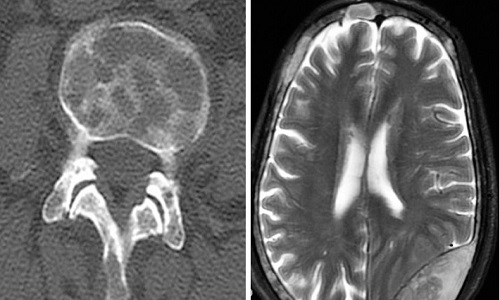

2.硬脑膜下积脓:可发生于颅骨骨髓炎之后,亦可因穿透性颅脑伤早期处理欠妥而引起感染。平时则常继发于严重的鼻副窦炎。早期病人常有头痛、发烧及颈强直等表现。稍后,逐渐出现颅内压增高如头痛、哎呀、视力下降及嗜睡等症状,但往往缺乏定位体征,较易漏诊。有时由于硬膜下积脓较大造成大脑半球受压或因皮质表面静脉血栓形成,亦可出现神经机能障碍,如偏瘫、失语或偏盲。此外,伴发局部性癫痫的机会较多,可达30%。确切的诊断有赖于脑血管造影、CT及MRI等影像学检查。脑血管造影不仅可以看到皮质血管远离颅骨内板,同时还能发现包绕在脓肿周围的肉芽组织毛细血管显影。CT平扫,早期多为紧靠颅骨内板下的新月形低密度区,常伴有大片脑水肿、脑炎、白质内梗塞灶及中线结构的明显移位。增强CT可出现边界清楚、厚度均匀的细强化带。当伴有皮质静脉栓塞和脑炎时,局部常出现脑回状强化影。MRI表现,在T1加权图像上信号低于脑实质,高于脑脊液,T2加权图像上信号高于脑实质,略低于脑脊液。